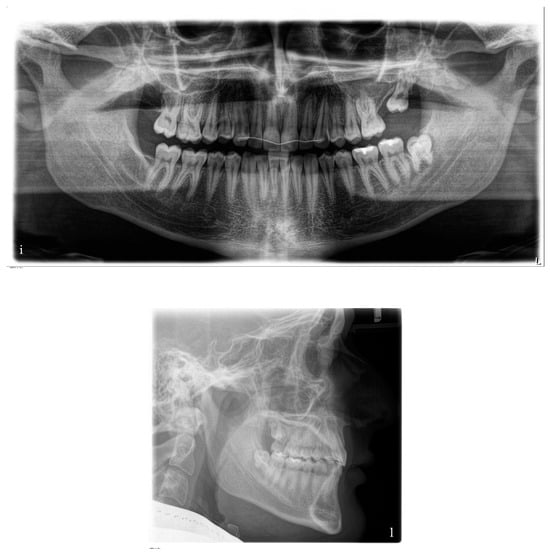

2.3. Case Description

2.4. Treatment Objectives and Alternatives

- The first option, corresponding to our choice, involved the distalization of the upper right quadrant in order to reach the molar and canine Class I occlusion and to correct the upper midline deviation. At the same time, it involved the mesialization of the upper left quadrant in order to close the spaces opened during the treatment.

- The second option involved the extraction of the upper right first premolar in order to correct the Class II canine relationship and the deviation of the upper midline.